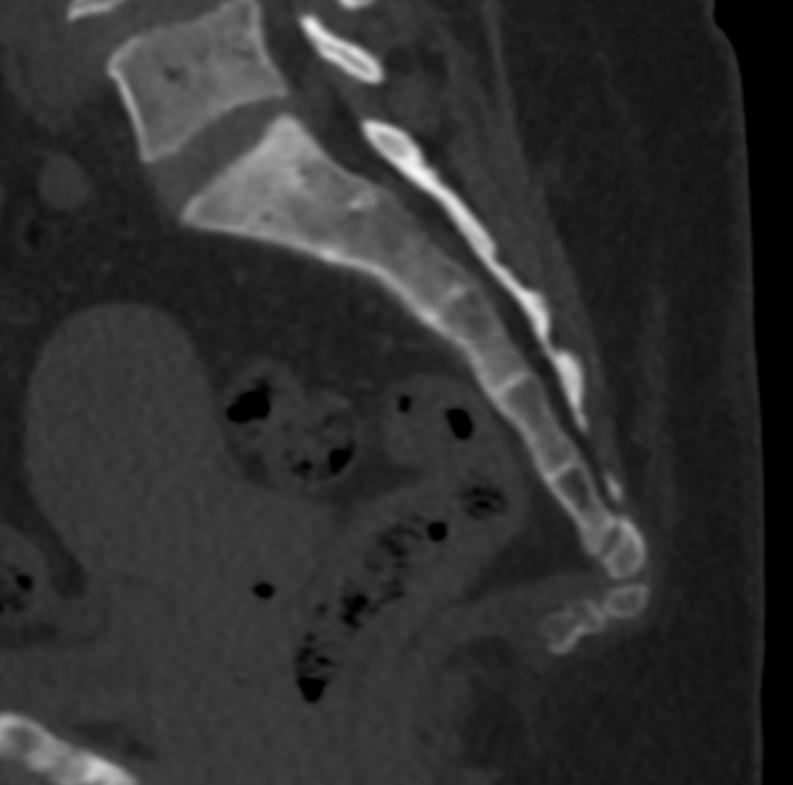

Для диагностики даже незначительных патологических изменений в различных отделах позвоночника, особенно в случае распространенного поражения, применяется один из современных наиболее информативных методов обследования – мультиспиральная компьютерная томография всего позвоночника. Методика основана на использовании проникающей способности рентгеновских лучей через органы и ткани человека и позволяет получить подробное изображение всех структур позвоночного столба. В комплексное обследование входит исследование шейного, грудного, пояснично-крестцового отделов позвоночника и копчика.

В медицинских центрах «Доступная медицина» сканирование всего позвоночника выполняется на новейших мультиспиральных компьютерных томографах последнего поколения TOSHIBA AQUILION в различных модификациях. Особенностью данных аппаратов является их способность проводить от 64 до 128 тончайших срезов одномоментно с минимальной толщиной от 0,5 мм.

Увеличенное количество высокочувствительных детекторов, которыми оснащены томографы, позволяет получать послойные снимки высокого качества с большой скоростью. Эта особенность данных аппаратов обеспечивает быстроту выполнения сканирования. При этом пациент получает минимальную дозу облучения, что имеет важное значение, особенно при такой обширной зоне исследования, как позвоночный столб.